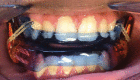

Continuous positive airway pressure (CPAP) is considered first-line treatment in the management of pediatric patients without a surgically correctible cause of obstruction who have confirmed moderate-to-severe obstructive sleep apnea (OSA). The evidence supports its reduction on patient morbidity and positive influence on neurobehavioral outcome. Unfortunately, in clinical practice, many patients either refuse CPAP or cannot tolerate it. An update on alternative approaches to CPAP for the management of OSA is discussed in this review, supported by the findings of systematic reviews and recent clinical studies. Alternative approaches to CPAP and adenotonsillectomy for the management of OSA include weight management, positional therapy, pharmacotherapy, high-flow nasal cannula, and the use of orthodontic procedures, such as rapid maxillary expansion and mandibular advancement devices. Surgical procedures for the management of OSA include tongue-base reduction surgery, uvulopalatopharyngoplasty, lingual tonsillectomy, supraglottoplasty, tracheostomy, and hypoglossal nerve stimulation. It is expected that this review will provide an update on the evidence available regarding alternative treatment approaches to CPAP for clinicians who manage patients with pediatric OSA in daily clinical practice.